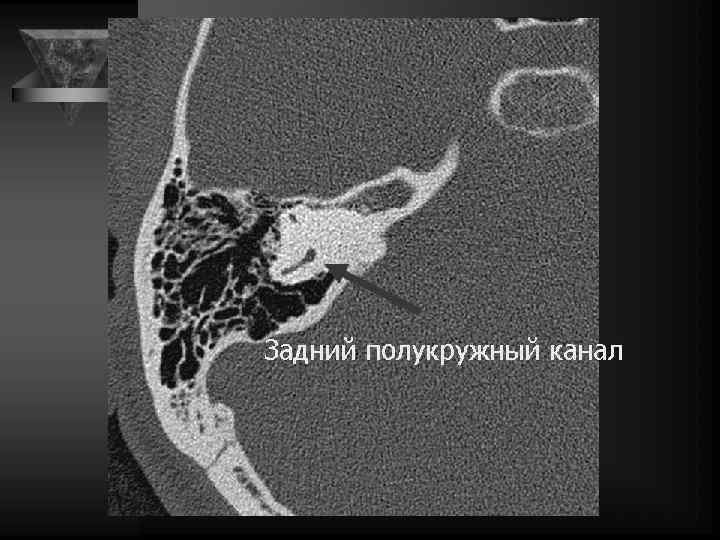

Нормальная анатомия 4 3 Улитка Верхний полукр. каналец Задний полукружный каналец Латеральный полукр. каналец

Внутреннее ухо и верхушка пирамиды • Улитка: деминерал-я костной капсулы, спирал-й канал улитки и его просвет, оссификация • Преддверие и полукружные каналы, интактные стенки, оссификация • Внутр. слух. проход: расширение, неровн-ть контура, деструкция кости, стеноз • Канал лицев. нерва до коленч. ганглия. • Водопровод преддв-я и водопр. улитки. • Верхушка пирамиды: губчатая или пневматизирована, наличие секрета, наличие образований